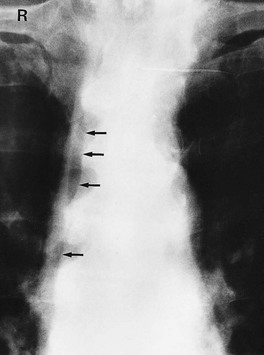

Fig. 5.8 Plain abdominal X-ray and IVU compared

(a) A plain abdominal film and (b) an intravenous urogram (IVU) of the same patient showing urinary tract stones. In the plain film, several calcified opacities (arrowed) are seen. From the IVU, in which the pelvicalyceal systems and ureters contain contrast material, it can be seen that three stones A lie within the lower right ureter and stone B lies within the upper calyces of the left kidney. On the right side, two other opacities C are seen to lie outside the urinary tract, probably representing calcified lymph nodes in the small bowel mesentery